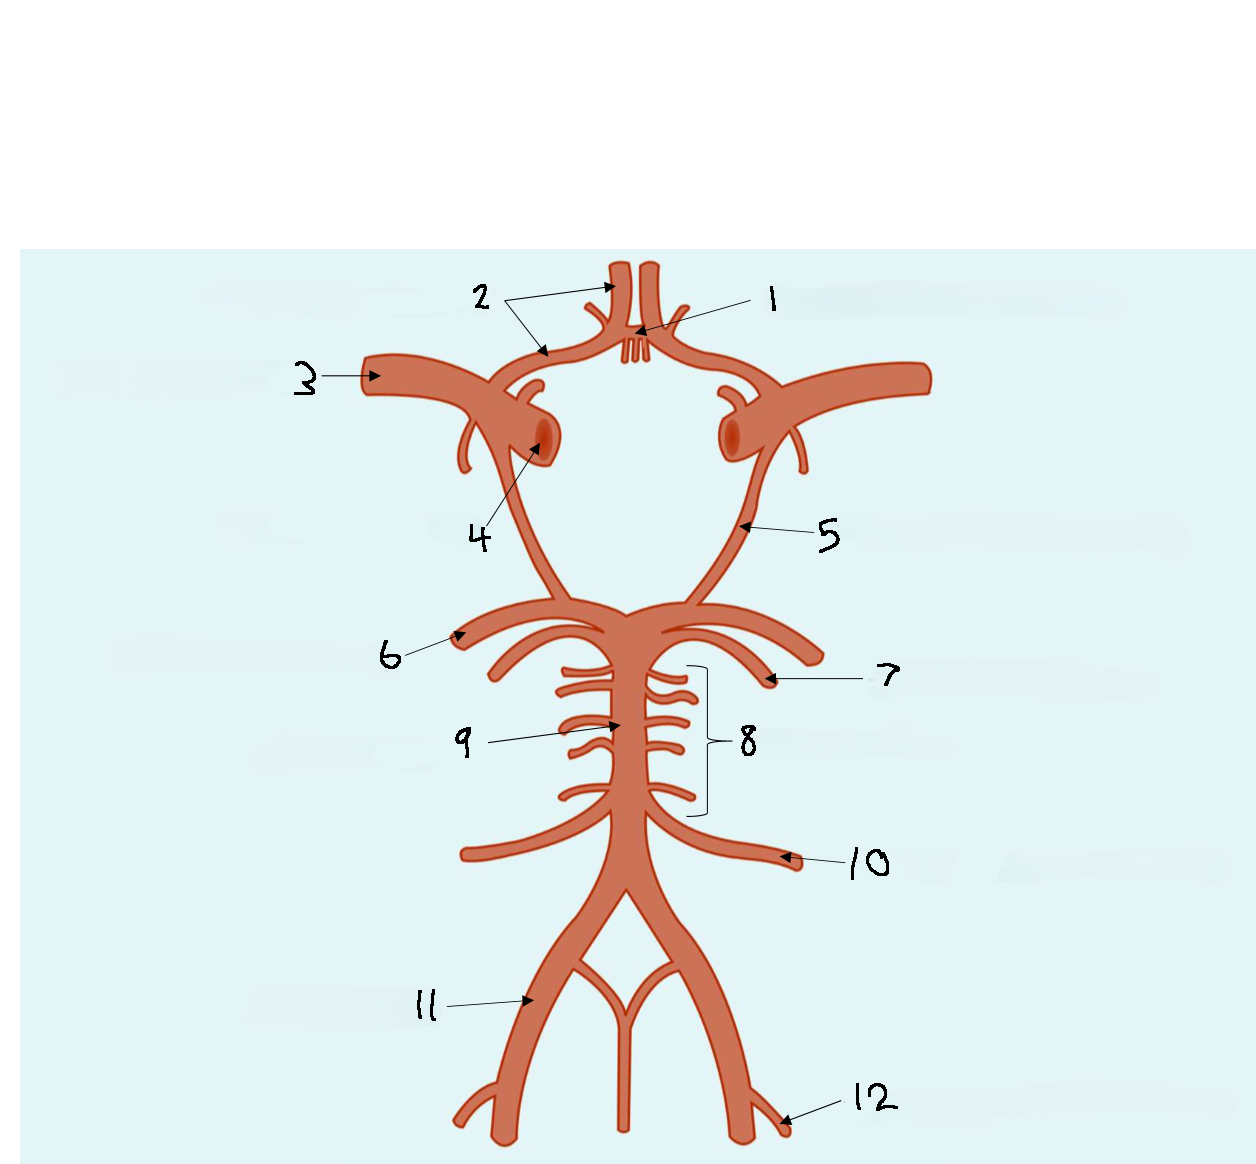

What is 1?

anterior communicating artery

What is 2?

anterior cerebral artery

What is 3?

middle cerebral artery

What is 4?

internal carotid artery

What is 5?

posterior communicating artery

What is 6?

posterior cerebral artery

What is 7?

superior cerebellar artery

What is 8?

pontine arteries

What is 9?

basilar artery

What is 10?

anterior inferior cerebellar artery

What is 11?

vertebral artery

What is 12?

posterior inferior cerebellar artery